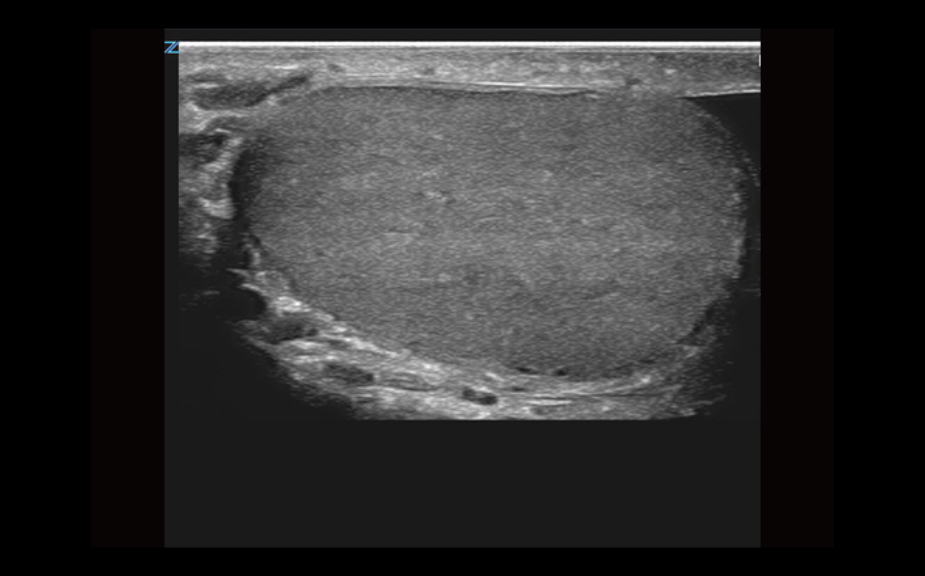

Equipped with patented, software based ZONE Sonography? Technology (ZST), the Z.One PRO provides optimally detailed B-mode and Doppler imaging for patients, regardless of body habitus, helping assure a reliable diagnosis.

Throughout a wide range of applications, the Z.One PRO is the ultrasound solution for your demanding clinical challenges.

- Unsurpassed image quality across all applications

The Z.One PRO is powered by ZONE Sonography Technology, an innovative and proprietary image formation architecture that acquires and processes acoustic data up to ten times faster than conventional beamforming methods.

The Z.One PRO ultrasound imaging platform offers a complete family of lightweight transducers that feature both extended broadband capabilities and multi-frequency flexibility delivering exceptional clarity and enhanced detail resolution even at the deepest depths. The C4-1 transducer can penetrate throughout the field of view while maintaining exception spatial and contrast resolution.